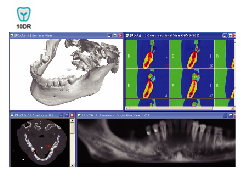

インプラント手術の成功は多くの重要なファクターと関係があります。神経管の位置、上下顎の構造、骨密度、適切な埋め込み位置とフィクスチャー(ネジ)の選択、かぶせものとの調和などです。このような色々な条件下で、より安全で信頼性の高い手術計画を立てるなら、10DRインプラントシステムが最適です。

10DR IMPLANTの機能は、既存のCTフィルムが提供した平面的で制限された情報の枠組を抜け出し、2次元/3次元イメージでバーチャルなインプラント手術シミュレーションを可能にしました。これにより手術の正確性が高まり、手術時に発生しうる、いろいろな問題を事前に探知してインプラント手術の危険性を最小限にし、安全な手術計画を可能にします。